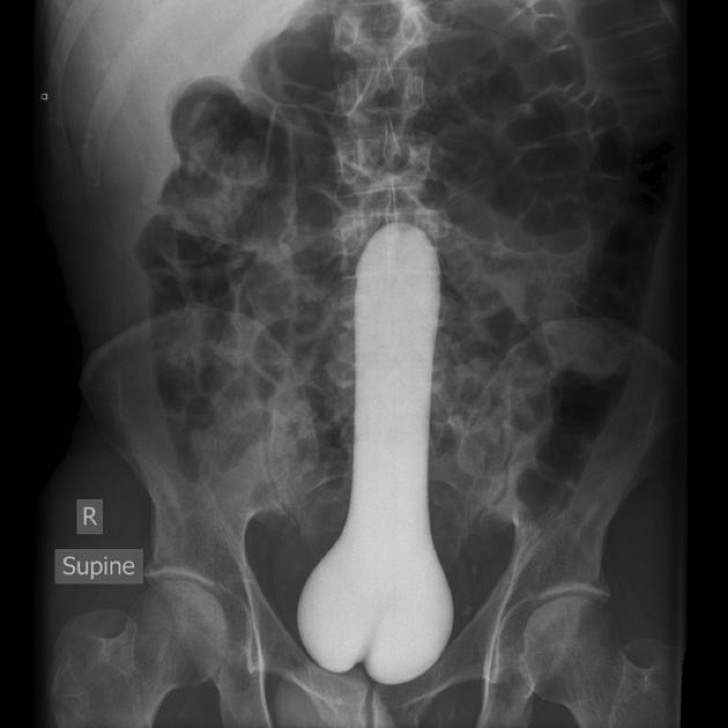

Este es un problema muy común. Si la persona no toma ningún medicamento que le esté provocando el problema, es necesario realizar exámenes para determinar la presencia de un tumor benigno en la base del cerebro, llamado microadenoma, el cual se manifiesta por cansancio, dolor de cabeza y pérdida del deseo sexual.